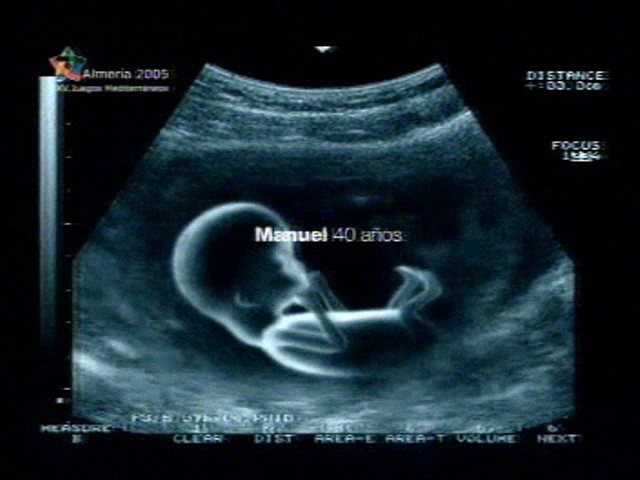

Sin embargo, las estrategias de seducción que hacen uso de los imaginarios sociales no son privativas de las marcas de cosméticos. En un anuncio de la marca de colchones Pikolin6 también se opera ese desplazamiento delirante que ya se daba en el caso anterior. En esta ocasión el spot comienza con una serie de imágenes en las que, sobre fondo negro, podemos leer lo siguiente: Ana, 30 años.

A continuación, sin que de por medio se de ningún otro efecto de transición, aparece la imagen de una ecografía, en plano medio largo, en la que se nos muestra un feto perfectamente formado, con las piernas y los brazos ligeramente doblados, disfrutando de un plácido sueño intrauterino. Resulta remarcable el hecho de que el mensaje que anteriormente aparecía sobre fondo negro queda ahora, tras un breve fundido, en el centro mismo de la pantalla.

Las apelaciones al imaginario del público espectador no pueden ser más evidentes. Mediante el uso de imágenes intercaladas de ecografías, así como de la referencia textual a personajes que en ningún caso aparecen en pantalla pero que se hallan representados por los fetos cómodamente instalados en su lecho intrauterino –recordemos que son Ana y Manuel, de 30 y 40 años, respectivamente –,el emisor de la comunicación visual nos da a entender que los colchones publicitados son, en términos de comodidad, verdaderos sucedáneos del útero materno, y que tan sólo en el interior de éste se podría gozar de un descanso tan cómodo y prolongado. La metáfora delirante, a la que anteriormente hacíamos alusión, se opera aquí de forma verdaderamente inesperada ya que el espectador, ante las imágenes que contempla, no puede hacer otra cosa más que identificarse no sólo con la mujer que se encuentra tumbada en el colchón de la marca publicitada, sino también probablemente con el feto que aparece en las ecografías. Cabe mencionar al respecto que para el psicoanálisis la fuente de la que mana la insatisfacción es precisamente la imposibilidad, inconsciente para el sujeto, de gozar de una completud semejante a esa completud primera de la que participa el feto aún nonato7. En definitiva, el spot parece querer decirnos que en los colchones anunciados nos sentiremos tal y como nos sentíamos en el útero materno, lo cual supone, siguiendo la trama narrativa del anunciante, la expresión pura de la comodidad y el sosiego.

Los registros sonoros del spot refuerzan la trama narrativa anteriormente mencionada. Los lentos acordes de una guitarra acústica acompañan a una voz masculina que canta, en inglés, una lenta canción que parece cumplir las funciones de una “nana”. El ambiente que muestran las imágenes, en su suceder fílmico, es de un sosiego absoluto, aún más teniendo en cuenta el sosiego que deben experimentar los fetos en el interior del útero materno. No hay cabida en la trama para la rapidez y fugacidad habituales en los spot publicitarios. Las imágenes permanecen en pantalla el tiempo suficiente para que el espectador tenga constancia de la envergadura de lo que contemplan sus ojos. Es, en definitiva, el anuncio de un sueño, el sueño que experimentamos en nuestra existencia intrauterina.

Tanto el plano denotativo como la dimensión connotativa del spot, en sus componentes plásticos e icónicos respectivamente, confluyen en una significación de tipo simbólica, esto es, marcadamente abstracta lindante a lo imaginario. Los planos de las ecografías, siempre tomados en una perspectiva lateral y a una distancia suficiente para que se aprecien los fetos en toda su magnitud; los colores claros, predominando los azules y los tonos blanquecinos, sugiriendo del mismo modo la pureza de un sueño sin interrupción ni mácula; los planos de la mujer, cuyos cabellos rubios concuerdan con el tono elegido por la trama narrativa del spot, vestida en color blanco y gris, siempre tenues y difusos. El desplazamiento, conducente a la identificación del espectador con aquello que contemplan sus ojos, es también evidente en este caso, lo que demuestra una vez más la pertinencia del análisis psicosocial del imaginario publicitario en todos los registros del spot televisivo, desde los más simples a los más elaborados. La estrategia de la seducción por medio del desplazamiento hacia el imaginario del espectador no es sólo privativa de un tipo de producto determinado, sino que atañe, cada vez más, a cualquier producto que quiera ser presentado como una apelación simbólica al espectador, esto es, como condensación de su propio imaginario.